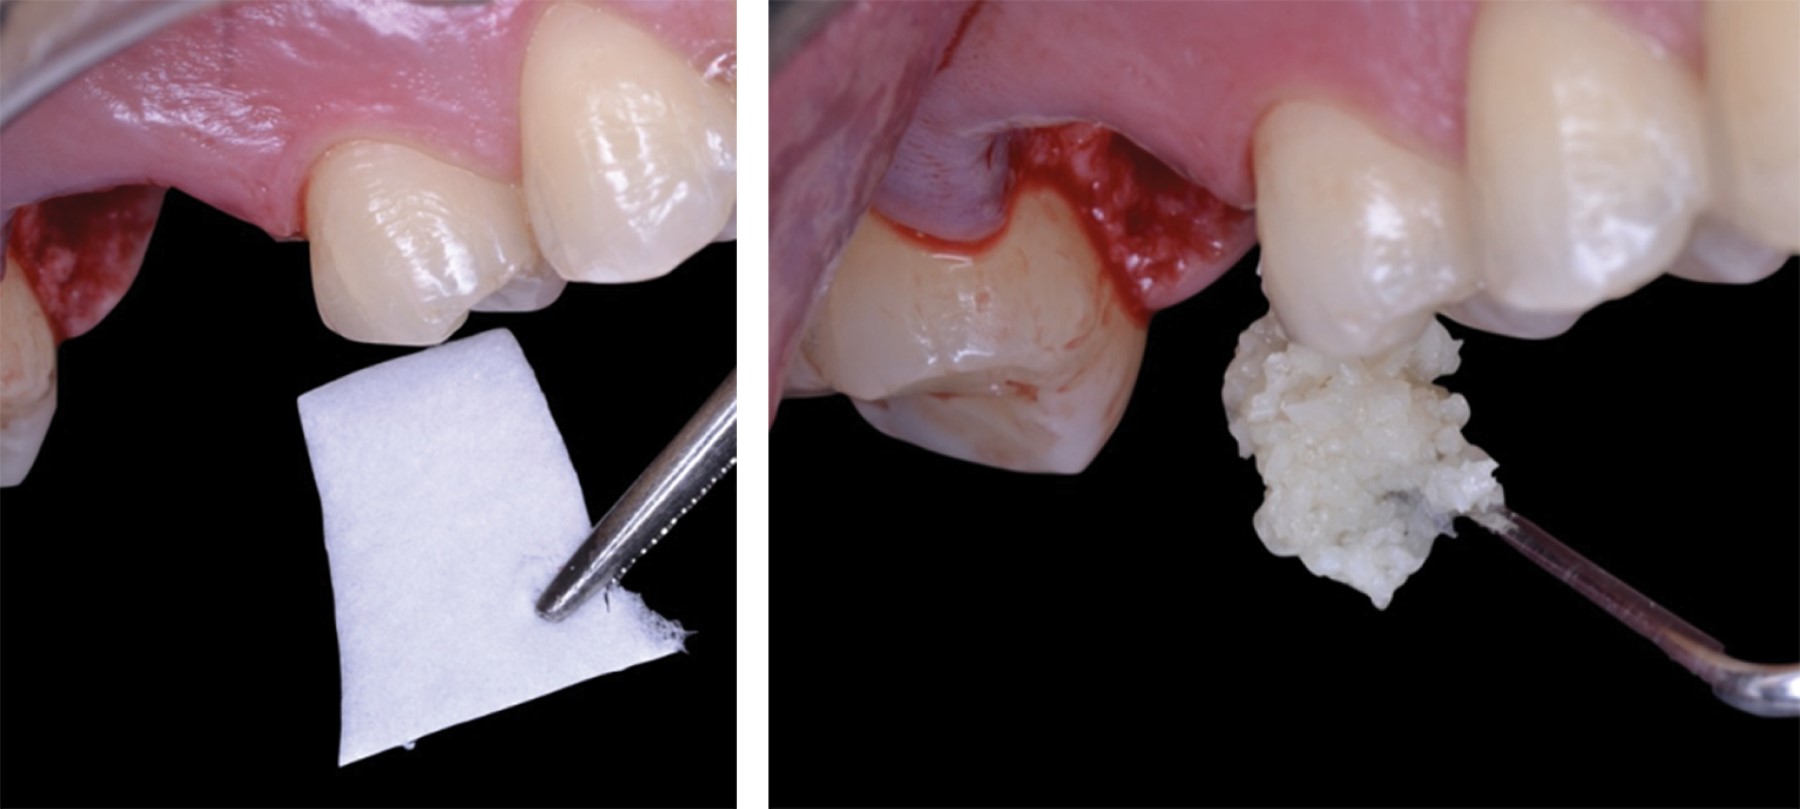

Se realizó fase higiénica periodontal (detartraje y profilaxis). Se citó al paciente para extracción y se llevó a cabo ARP; se colocó una matriz colágena (MatrixDerm Tape) en los ápices del alveolo y se colocó injerto óseo de tipo aloinjerto2,9 (Allograft-LifeNet Health) (Figura 3). Se seleccionó la técnica de colgajo pediculado de paladar de tejido conectivo subepitelial para cubrir el alveolo.9

Se realizó una incisión paramarginal palatina, en promedio a dos milímetros apical de la recesión palatina (margen gingival) desde la porción distal del segundo molar superior derecho hasta la porción mesial del segundo premolar superior derecho, y una descarga distal (diseño descrito por Liu y colegas.)22 y se reflejó un colgajo mucoperióstico para obtener acceso al tejido conectivo donante (Figura 4).9

Después se realizó una incisión aguda del tejido subepitelial, paralela a la primera incisión para obtener un injerto de tejido conectivo (se buscó mantener un grosor constante de dos milímetros,15 dejándolo pediculado en la región posterior) (Figura 5). Se colocó una matriz colágena sobre el injerto óseo, se elevó el colgajo de tejido conectivo subepitelial, se tunelizó por debajo de la porción palatina y se rotó para cubrir el defecto (Figura 6).

Figura 3

Figura 4